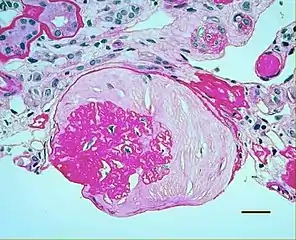

In benign nephrosclerosis, the changes occurring are gradual and progressive, however, there can be sufficient kidney reserve capacity to maintain adequate kidney function for many years.[10] The large renal arteries exhibit intimal thickening, medial hypertrophy, duplication of the elastic layer. The changes in small arterioles include hyaline arteriolosclerosis (deposition of hyaline, collagenous material), which causes glomerular collapse (wrinkling and thickening of capillary basement membranes and collapse of capillary lumen) and solidification (glomeruli exhibit sclerosis and increase in mesangial matrix). The degree of scarring correlates with the degree of glomerular filtration deficit.

Light micrograph showing hypertensive glomerular lesion of hypertensive nephropathy: global glomerular collapse and filling of Bowman's space with a lightly staining collagenous material.

Light micrograph showing hypertensive glomerular lesion of hypertensive nephropathy: global glomerular collapse and filling of Bowman's space with a lightly staining collagenous material. Light micrograph of glomerulus showing secondary segmental sclerosis of hypertensive nephropathy.

Malignant nephrosclerosis is where hypertensive nephrosclerosis occurs in presence of malignant hypertension (when DBP > 130mmHg).[11] Vessels feature intimal thickening, fibrinoid necrosis, red blood cell fragmentation, extravasation, thrombosis. These changes create an exaggerated layered appearance (onion skinning).[12]